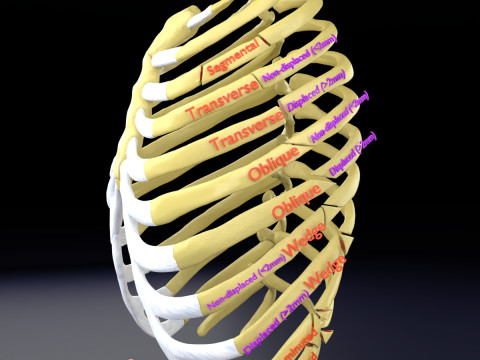

This is a 1:1 scaled model of right breast cut opened in sagittal plane to reveal its internal antomy and histology (schematic). The deeper parts and fascial layers are also depicted to give a very detailed approach to the model. The full layers starting from skin, nipple areola, till intercodtal muscles and ribs are also depicted.